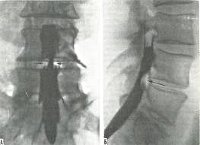

Миелография. Рентгеноконтрастное исследование субарахноидального пространства спинного мозга. Техника назначается при симптомах сдавления спинного мозга или его корней неизвестной этиологии, подозрении на сирингомиелию, арахноидит, злокачественные и доброкачественные новообразования, некоторые другие заболевания. Исследование может быть восходящим или нисходящим, в первом случае введение контрастного вещества производится путем люмбальной пункции второго субокципитала. Из-за широкого распространения методов исследования, таких как магнитно-резонансная томография и компьютерная томография, миелография редко используется из-за сложности и неопределенности процедуры.

Миелография